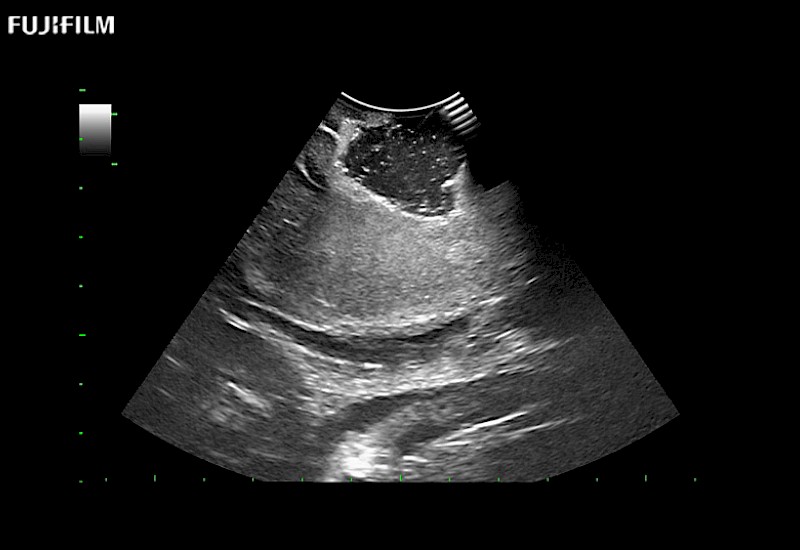

Tight curved (12mm) array transducer that is ideal for scanning during cranial guidance procedures.

Main Specifications: